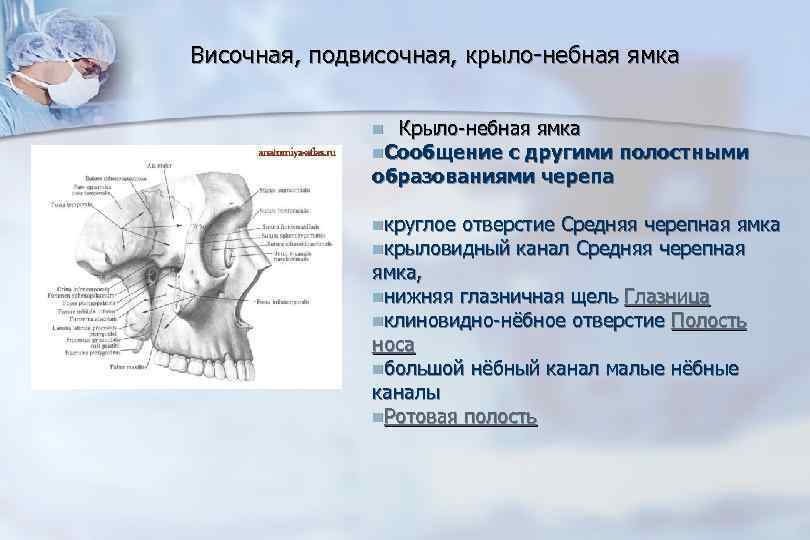

Анатомические особенности: фотографии ямок черепа, височной и подвисочной крылонебной